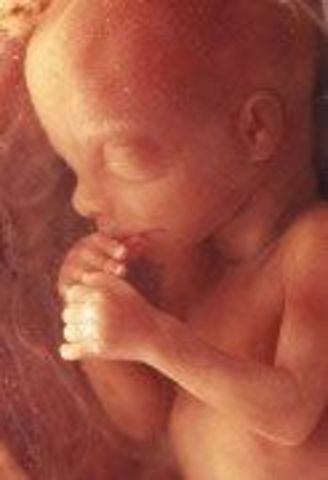

• Week Twenty Five: Exploration continues

Week Twenty Five: Exploration continues

Bones are becoming solid, hands are now fully developed. The brain is growing rapidly, the brain cells are starting to mature. The sexual organs are fully developed.

• Week Twenty Six: Second trimester ends this week

Week Twenty Six: Second trimester ends this week

The feet are 2 inches (5cm) long. Hands are very active. The baby's eyes begin to open around this time.